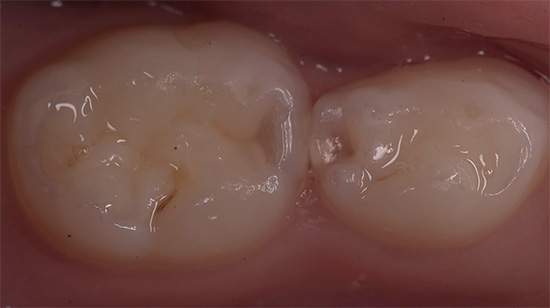

Etapas do tratamento de cárie profunda

O tratamento da cárie profunda consiste em uma série de etapas realizadas pelo dentista na ordem necessária para a situação clínica em questão.

- E, finalmente, a formulação do selo, selecionado de acordo com as características da cavidade a ser preenchida.